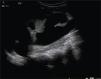

Presentación de los casosCaso 1Masculino de 12 años de edad, con antecedente de infecciones urinarias recurrentes desde los 7 meses de edad. Presenta incontinencia urinaria continua. Es manejado anteriormente con cateterismo limpio intermitente al parecer sin adecuado apego, no mostrando mejoría. Presenta una creatinina sérica de 0.7mg/dL con urea de 49mg/dL, el examen general de orina muestra: leucocituria, bacterias abundantes, nitritos positivos y proteinuria de 300 mg/dL. Presenta un cultivo positivo para Escherichia coli (E. coli) > 100,000 UFC; se indica tratamiento con antibiótico. En la cistografía se evidencia una vejiga de esfuerzo, con reflujo vesicoureteral G-5 derecho y abundante orina residual (fig. 1). El ultrasonido muestra ectasia renal derecha severa y ectasia moderada izquierda (fig. 2). La resonancia magnética de columna se encuentra normal y la valoración por Neurocirugía corrobora que no hay alteración neurológica, la cistoscopia reveló que no hay valvas uretrales. Se realiza ampliación vesical con sigmoides más estoma de Mitrofanoff, se maneja con cateterismo limpio intermitente a través del estoma. En el seguimiento presenta mejoría clínica notable a razón de cese de las infecciones, disminución de ectasia renal (fig. 3), así como desaparición del reflujo vesicoureteral (fig. 4) y continencia completa entre los cateterismos.